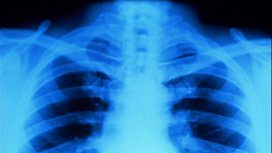

Medical: Pulmonary embolisms

We look at the warnings signs of pulmonary embolisms: blocked blood vessels in the lungs.